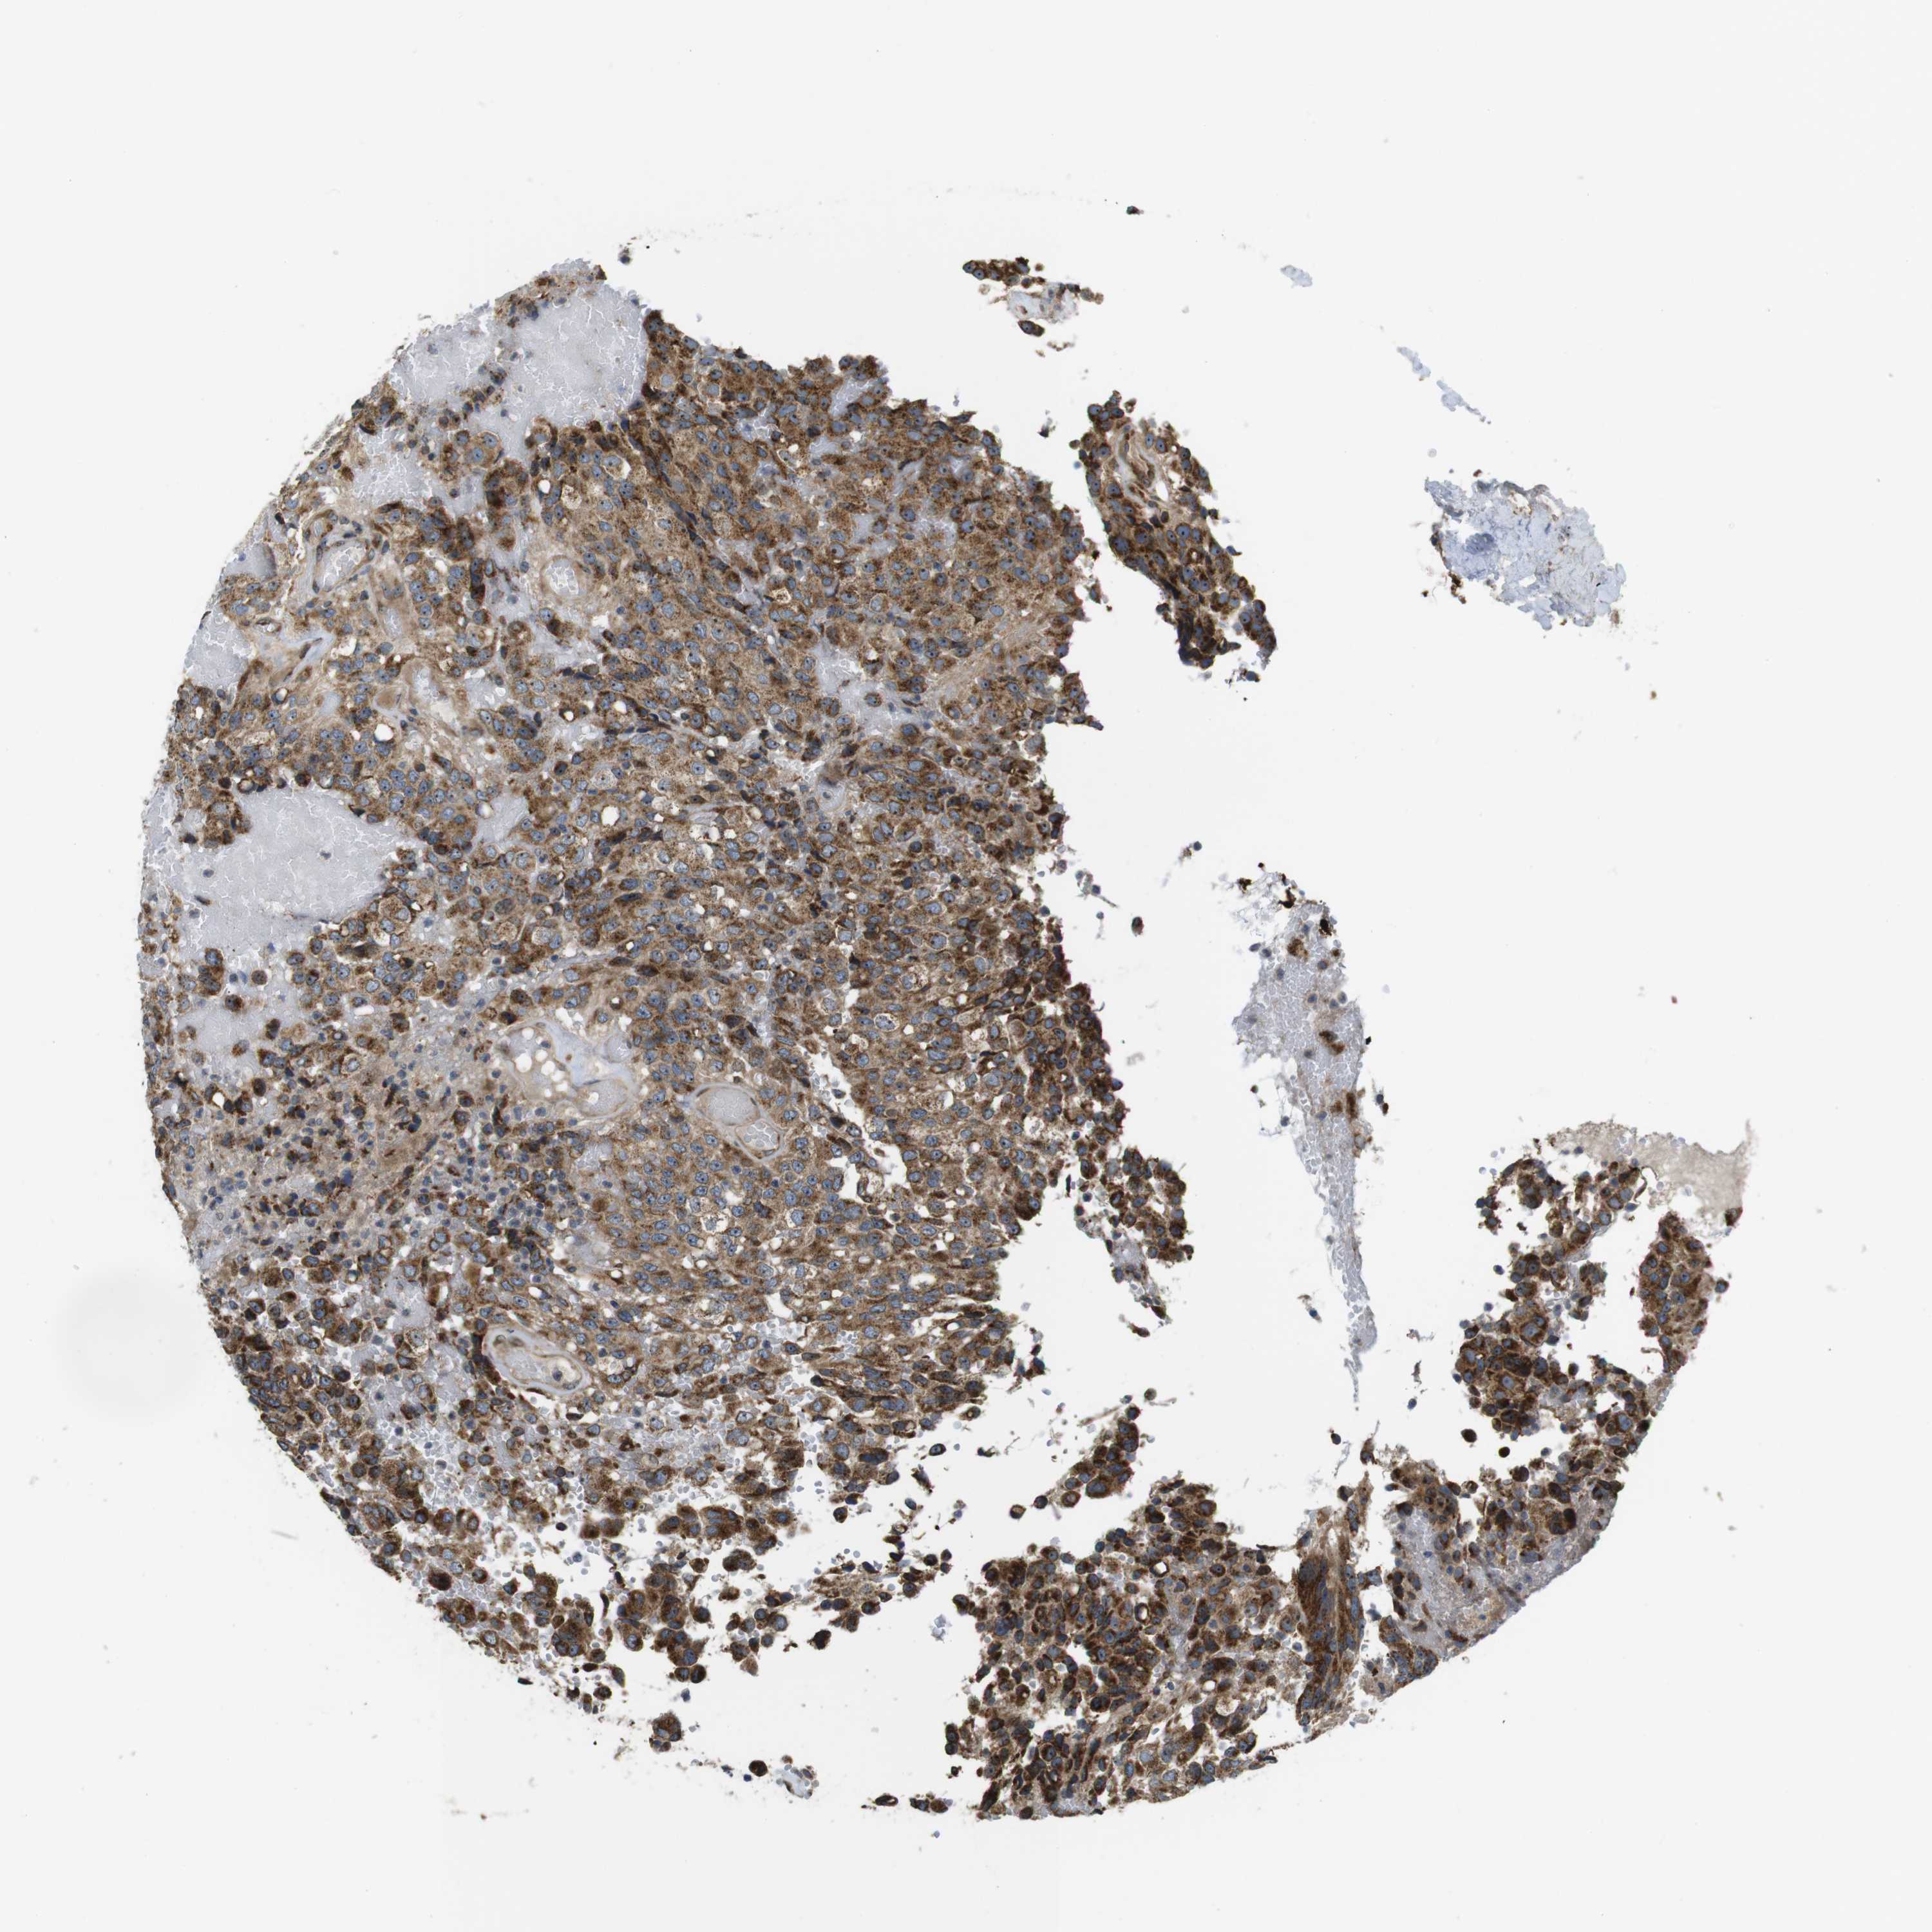

GLIOMA - Protein expressioni

A mouse-over function shows sample information and annotation data. Click on an image to view it in a full screen mode. Samples can be filtered based on level of antibody staining by selecting one or several of the following categories: high, medium, low and not detected. The assay and annotation is described here.

Note that samples used for immunohistochemistry by the Human Protein Atlas do not correspond to samples in the TCGA dataset.

Antibody stainingi

Antibody staining in the annotated cell types in the current human tissue is reported as not detected, low, medium, or high, based on conventional immunohistochemistry profiling in selected tissues. This score is based on the combination of the staining intensity and fraction of stained cells.

Each image is clickable and will lead to virtual microscopy that enables deeper exploration of all samples and also displays staining intensity scores, fraction scores and subcellular localization as well as patient and tissue information for each sample.

Antibody HPA014476

Antibody HPA058645

Staining

High

Medium

Low

Not detected

Intensity

Strong

Moderate

Weak

Negative

Quantity

>75%

75%-25%

<25%

None

Location

Nuclear

Cytoplasmic/membranous

Cytoplasmic/membranous,nuclear

Glioma, malignant, High grade

Glioma, malignant, Low grade